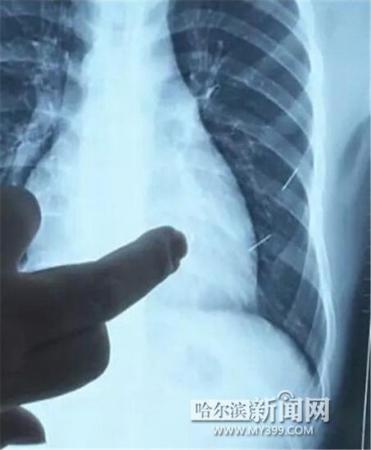

醫(yī)生指出X光片上的針狀物

昨日上午,記者在哈醫(yī)大二院第八住院部心外三病房找到了躺在病床上痛苦不堪的董立仁,家屬正在他身旁不斷安慰著他。見記者前來,董立仁母親李百燕拿出一張X光片,上面可以清晰地看到胸腔內(nèi)一共有4根針狀物,其中一根在心臟部位,兩根在胸腔壁上,還有一根在腹腔壁上。

心外三病房董立仁的主治醫(yī)生告訴記者,董立仁送到醫(yī)院時(shí)病情很危險(xiǎn),隨時(shí)可能危及生命?!巴ㄟ^檢查發(fā)現(xiàn),他心臟內(nèi)有一個(gè)金屬異物,正好在心臟上。心臟每次跳動(dòng)都與其產(chǎn)生摩擦,導(dǎo)致出血,心包積液懷疑是血液。如果大量出血會(huì)凝結(jié)成血塊,血塊包裹住心臟就會(huì)影響心臟跳動(dòng),隨時(shí)都有停跳的危險(xiǎn)。心臟上的異物是致命傷,其余胸腔壁和腹腔壁的異物傷害不大?!?/p>

昨天16時(shí)30分左右取針手術(shù)開始。因鋼針隨時(shí)會(huì)危及患者生命,此次手術(shù)定義為大型手術(shù)。開胸后,醫(yī)生打開董立仁心包,發(fā)現(xiàn)一枚鋼針已深深扎入心臟,僅露出1厘米長度在外。拔出鋼針后,醫(yī)生發(fā)現(xiàn),這枚針長達(dá)5厘米。受鋼針影響,心包出現(xiàn)大量積液,近800毫升。

隨后,在下胸壁位置,第二枚鋼針順利取出。在尋找另兩枚鋼針過程中,普外、胸外多名醫(yī)生也參與手術(shù),為主刀醫(yī)生提供更為穩(wěn)妥的處理建議。根據(jù)X光片顯示位置,醫(yī)生未在患者體內(nèi)找到剩余兩枚鋼針。醫(yī)生懷疑,其中一枚鋼針可能深藏在肋骨骨膜位置,無法尋找,最后決定結(jié)束手術(shù),做進(jìn)一步觀察,研究下一次手術(shù)方案。